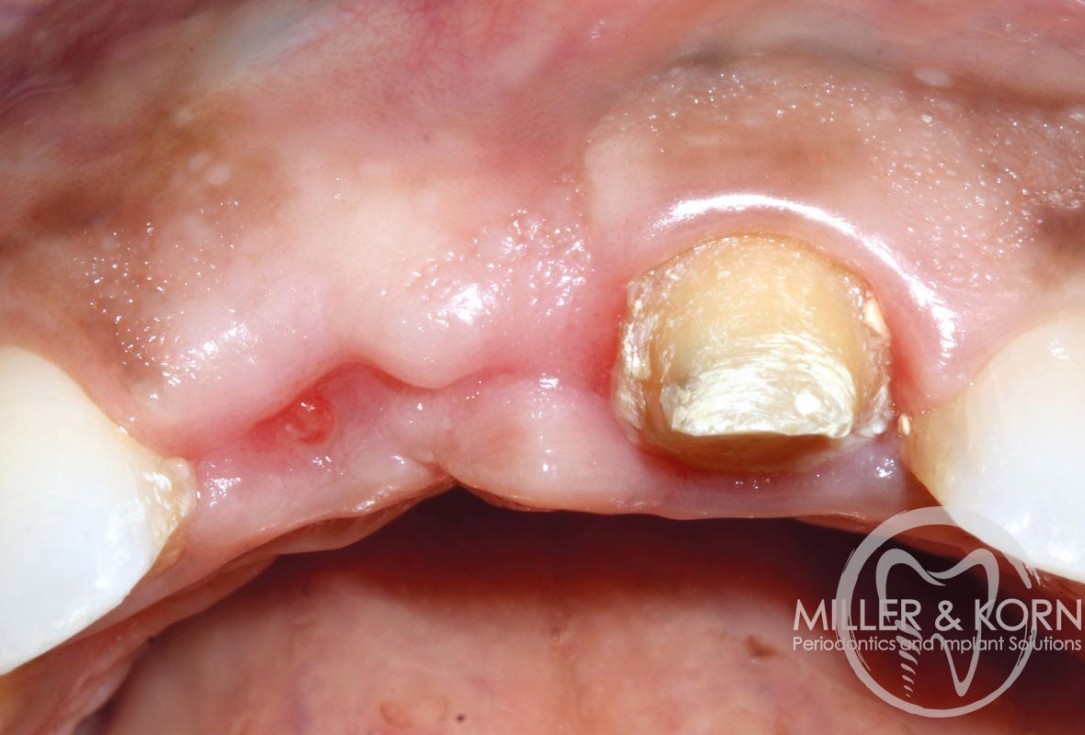

18/22 - Placement of healing abutment. Note buccal convexityImmediate implant placement and regeneration of ridge using an allograft bone ring and Jason® membrane - Drs. Miller and Korn